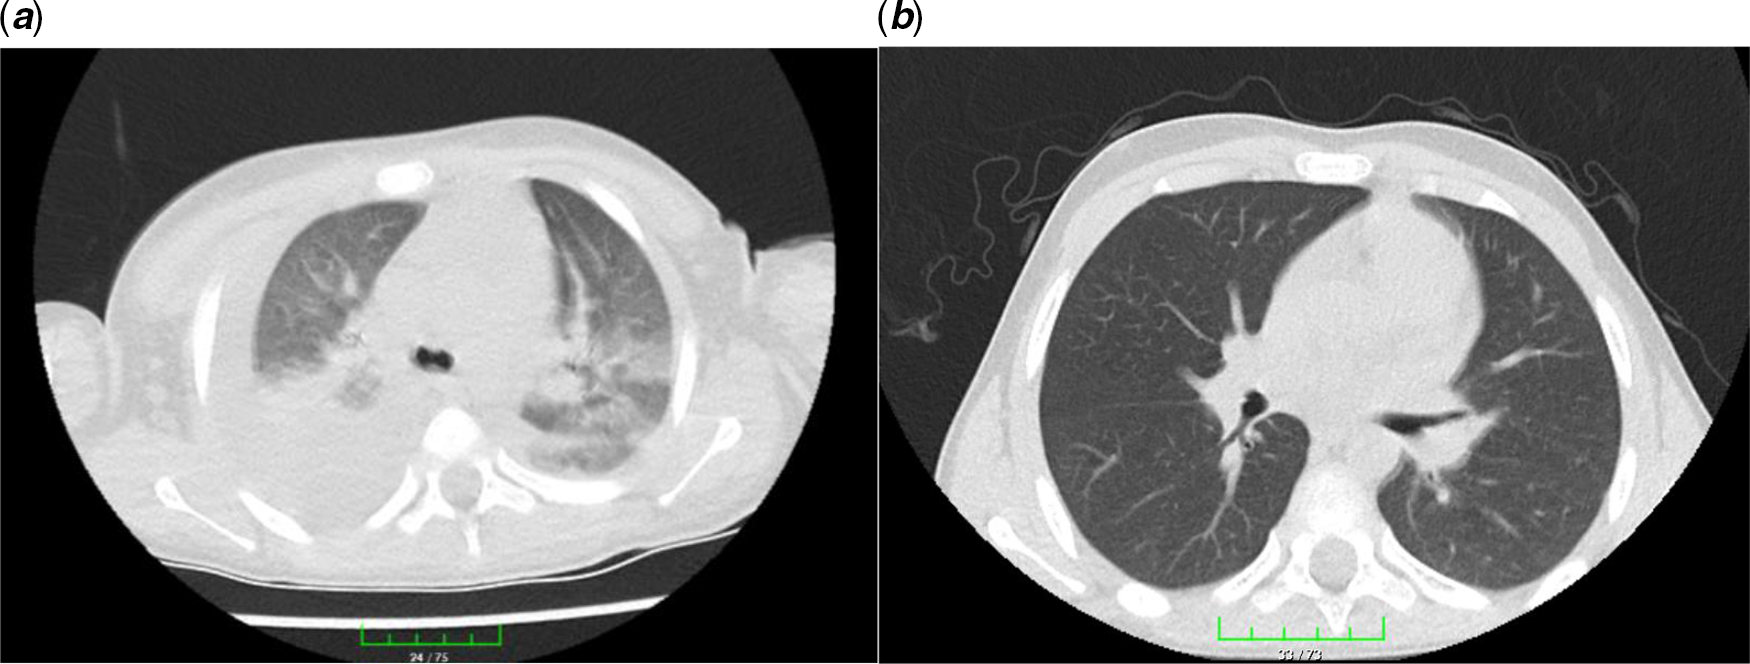

On admission, he was not dyspnoeic with a body temperature of 39.2°C. Nasopharyngeal/oropharyngeal swabs (NP/OP) swabs were sent to the reference laboratory and tested negative for 2019 novel coronavirus by a real-time reverse transcriptase polymerase chain reaction assay. Other respiratory pathogens were also negative. Initial laboratory results were as follows: white blood cell count 6040/μL (27.3% lymphocytes), haemoglobin 10.6 g/dL, platelet count 116,000/μL, serum Na 129 mEq/L, and serum albümin 3.1 g/dL. Figure 1 showed the course of inflammatory parameters at the admission and during treatment. His chest radiological imaging (X-ray and high-resolution CT) showed pneumonic infiltrates with predominance on the right (Figs 2 and 3). Echocardiographic study revealed normal left ventricular functions and coronary arteries. Pericardial effusion and mitral regurgitation were not present. It was diagnosed that he had Kawasaki disease and COVID-19 infection because of positive family history and patchy or nodular consolidations with peripheral ground-glass opacities in subpleural areas although negative swap polymerase chain reaction result. Treatment was started with ampicillin-sulbactam (250 mg/kg/day ampicillin; sulbactam IV divided every 6 hours), azithromycin (15 mg/kg/day), oseltamivir (60 mg twice daily), and hydroxychloroquine (10 mg/kg/initial dose; 6 mg/kg twice daily). Two main treatments for Kawasaki disease are aspirin and intravenous immune globulin. Because aspirin may cause side effects, including Reye’s syndrome, clexan (100 IU/kg/dose BD) was added to reduce blood clots. After the first intravenous immune globulin dose (2 gr/kg/dose), his fever did not improve. So, the second dose of intravenous immune globulin was given. The serologic test for the presence of IgM and IgG antibodies in plasma against COVID-19 was weakly positive. On hospital day 4, his fever decreased but pneumonia progressed (Figs 2 and 3). He had dyspnoea and complained of a nonproductive cough. SpO2 decreased to 75%. He needed high-flow nasal canula oxygen therapy, but not intubation. Oseltamivir and hydroxychloroquine were stopped and lopinavir/ritonavir (300/75 mg/day) was started. Azithromycin therapy was stopped on hospital day 5. Treatment with ampicillin-sulbactam was continued for 10 days.

Figure 3. Chest high-resolution CT: from left to right. (a) Patchy or nodular consolidations with peripheral ground-glass opacities in subpleural areas and (b) resolution after 14 days of lopinavir/ritonavir therapy.

Lopinavir/ritonavir treatment was continued for 14 days. He was discharged with just acetylsalicylic acid therapy (150 mg/day) on hospital day 18. His overall clinical condition improved, with increasing appetite, and he was afebrile. During hospitalisation, repeated echocardiographic examinations were done and no new coronary pathology developed. On lopinavir/ritonavir treatment 14, the radiological improvement was complete (Figs 2 and 3). The serologic test (IgM/IgG antibodies) in plasma against COVID-19 was continuingly strong positive.

Thorax CT is a sensitive diagnostic approach in the early period in patients with a negative polymerase chain reaction test for COVID-19. Reference Park, Han, Park, Kim and Choi2 Ai et al Reference Ai, Yang and Hou5 reported that 94% of patients had bilateral chest findings and they had ground-glass opacities (49%) and consolidation (55%). Also, Zhu et al Reference Zhu, Xie, Lu, Xu, Zhou and Fang6 showed that 97% of patients had bilateral chest findings and frequency of radiological findings were ground-glass opacities (50%); consolidation (13%); spider web sign (13%); crazy-paving pattern (3%); and pleural effusion (7%). Our patient had consolidation, spider web sign, and patchy or nodular consolidations with peripheral ground-glass opacities.